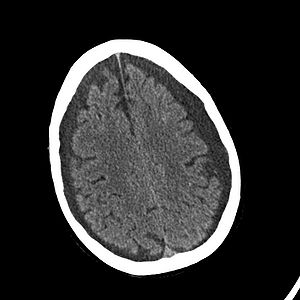

Indtryk af hygromer | Indtryk af cerebrale hygromer evt. under hastig udvikling. Skyldes liquorfistel i spinalkanalen som resulterer i et lavt tryk i spinalkanalen, hvorved hjernen displaceres caudalt og derved obstruerer det normale CSV-kredsløb. Resultatet er forhøjet ICP og hygromdannelse. | ||

Indtryk af cerebrale hygromer evt. under hastig udvikling. Skyldes liquorfistel i spinalkanalen som resulterer i et lavt tryk i spinalkanalen, hvorved hjernen displaceres caudalt og derved obstruerer det normale CSV-kredsløb. Resultatet er forhøjet ICP og hygromdannelse.

Radiologi